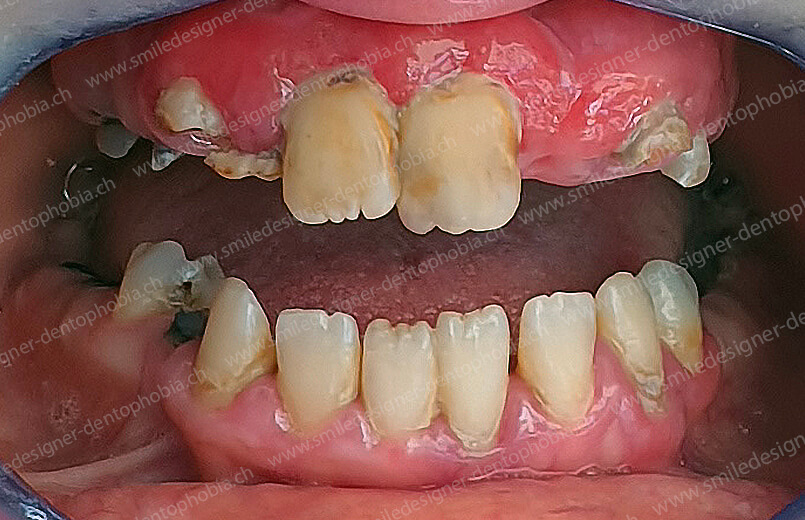

Cas clinique « DOMINO SURGERIES MCI » : Bridge implanto-porté avec extensions postérieures (ALL ON 6/6).

Version intermédiaire des bridges de première intention de Mise en Charge Immédiate (MCI) pour une resocialisation immédiate de la patiente cas en cours de cicatrisation des sinus lift et en attente des futurs implants postérieurs maxillaires.

- Sans période sans dents : des bridges provisoires en composite sont posés dès la première intervention.